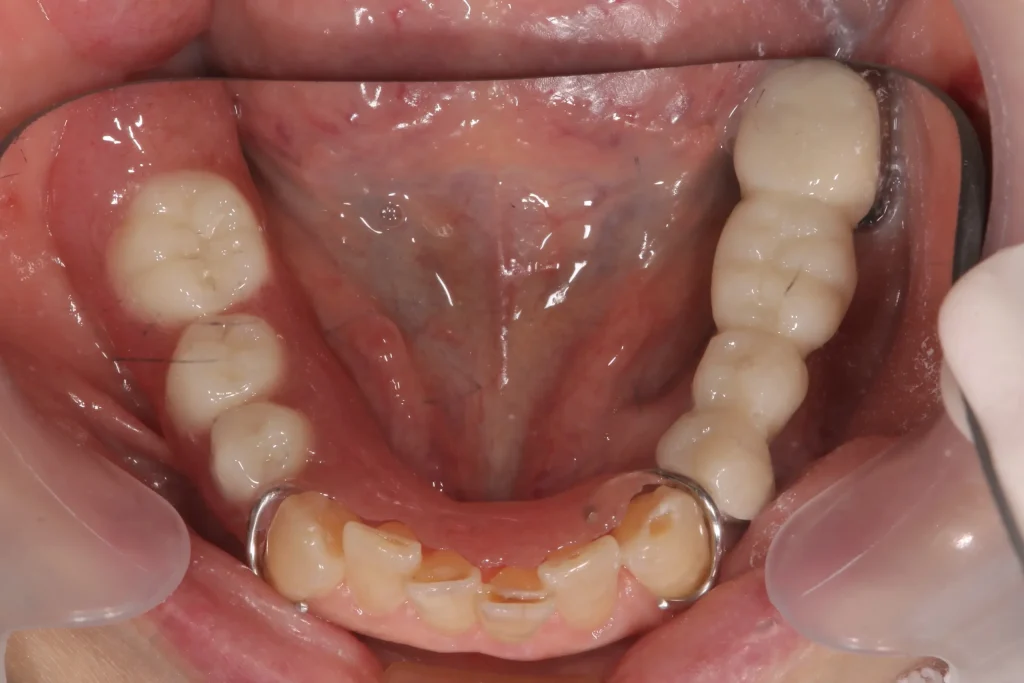

🟦歯を抜いた後の3つの治療法の比較

① 入れ歯

② ブリッジ

③ インプラント